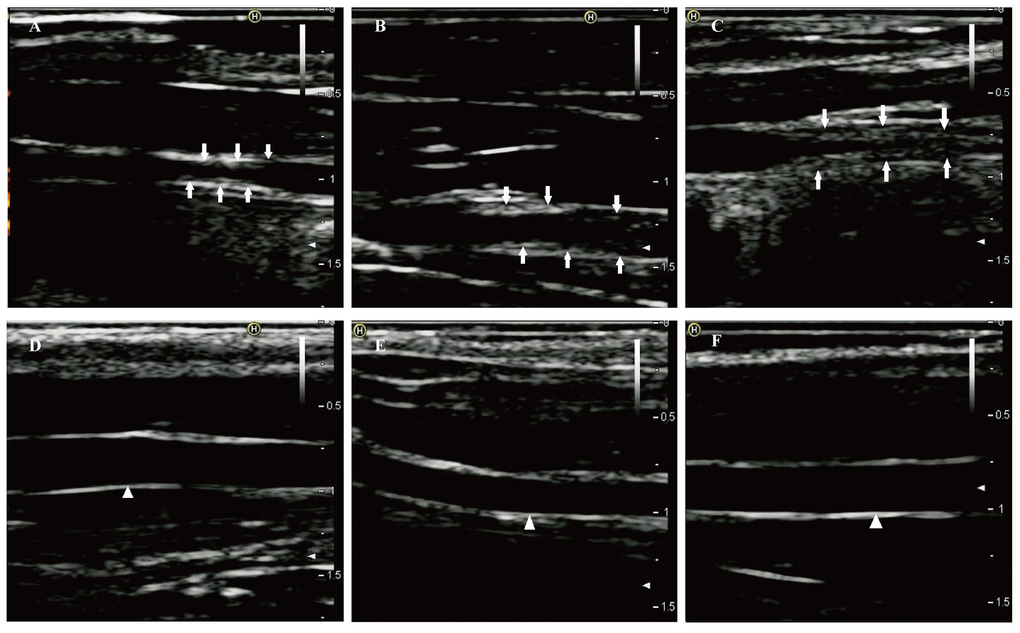

After one week of endothelial injury and high-fat diet, atherosclerotic plaques appeared. The atherosclerotic plaques of the right common carotid arteries were easily detected by the 8th week on the 2D-ultrasound images (Figure 1A-C). However, the carotid arteries of rabbits in the control group had no significant changes and the intima remained smooth (Figure 1D-F). Besides, hematoxylin and eosin stained vessels adjacent to the RNA samples revealed plaques of different severities in the carotid arteries of the case group (Figure 2A-C), while there were no obvious abnormalities in the control group (Figure 2D-F).

Figure 1. Two-dimensional ultrasound of right common carotid arteries at eighth week. (A-C) Two-dimensional ultrasound images show that the right common carotid arteries in the case group formed obvious atherosclerotic plaques indicated by the arrows. (D-F) Two-dimensional ultrasound images clearly show that the intimas of the right common carotid arteries in the control group remain smooth (white triangle).